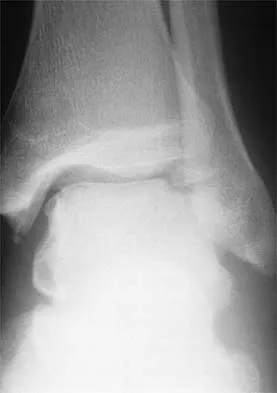

Figures 38a and 38b show the CT scans of a 64-year-old woman. What is the most likely diagnosis?

The CT scans show large cystic lesions in the talus and calcaneus with complete subluxation of the subtalar joint, allowing the calcaneus to slide laterally until it becomes blocked by the fibula. The cause of this subluxation is severe posterior tibial tendon dysfunction. Although no fibular fracture has yet appeared, it can occur with continued stress from the calcaneus. There is, however, a pathologic fracture in the medial calcaneus through a medial degenerative cyst. The joint space is irregular and not symmetrical as would be seen in an inflammatory arthropathy. Cystic lesions are not present in the tibia. No stress fracture is seen in the talus. Coughlin MJ: Sesamoids and accessory bones of the foot, in Coughlin MJ, Mann RA (eds): Surgery of the Foot and Ankle, ed 7. St Louis, MO, Mosby, 1999, pp 437-499.